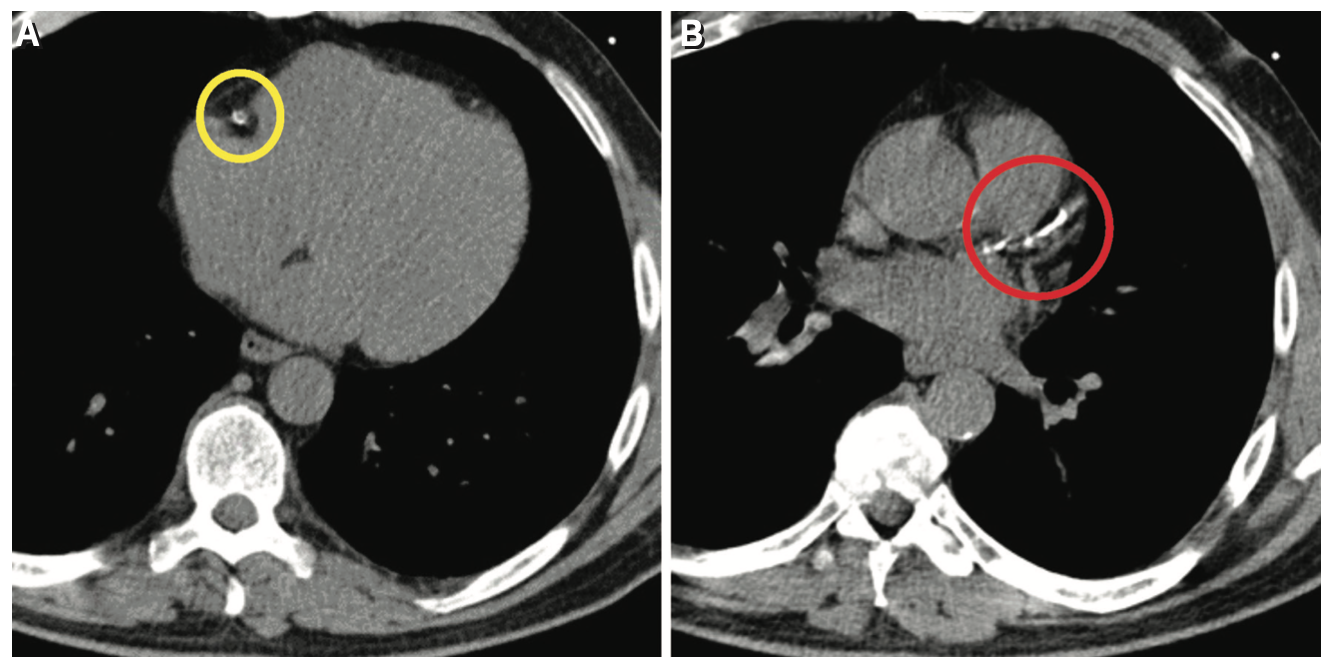

The main limitations of CT calcium scoring are that it is an out-of-pocket expense unless it is authorized by insurance as part of a CCTA exam. There is also potential for incidental findings due to the display field of view that is used to obtain the scan (Figure 2). Since the display field of view covers the heart and much of the mediastinum, incidental extra-cardiac findings have been reported that may lead to unnecessary follow-up studies and treatments.3

Once the location of the aortic root is identified on the unenhanced scan by the CT technologist, the second enhanced scan starts with a 10 mm scan coverage acquired during the initial IV contrast bolus technique, allowing for optimal peak enhancement to the aortic valve. A third scan is initiated, serving as the final portion of the CTA of the chest, abdomen, and pelvis, or whole-body scan. The whole-body CTA evaluates the entire aorta, ilio-femoral arteries, and coronary arteries. The whole-body study guides the physician in obtaining vascular access, as it can visualize the tortuosity of the aorta and the vascular access routes (iliofemoral, subclavian, trans-apical, or direct aorta). CTA is also essential to identify patients with increased anatomical risk for coronary artery occlusion in valve-in-valve (ViV) procedures (Figure 8). CTA is also very useful in the evaluation of late complications, such as perivalvular leaks, thrombosis, and valve displacement.12,13